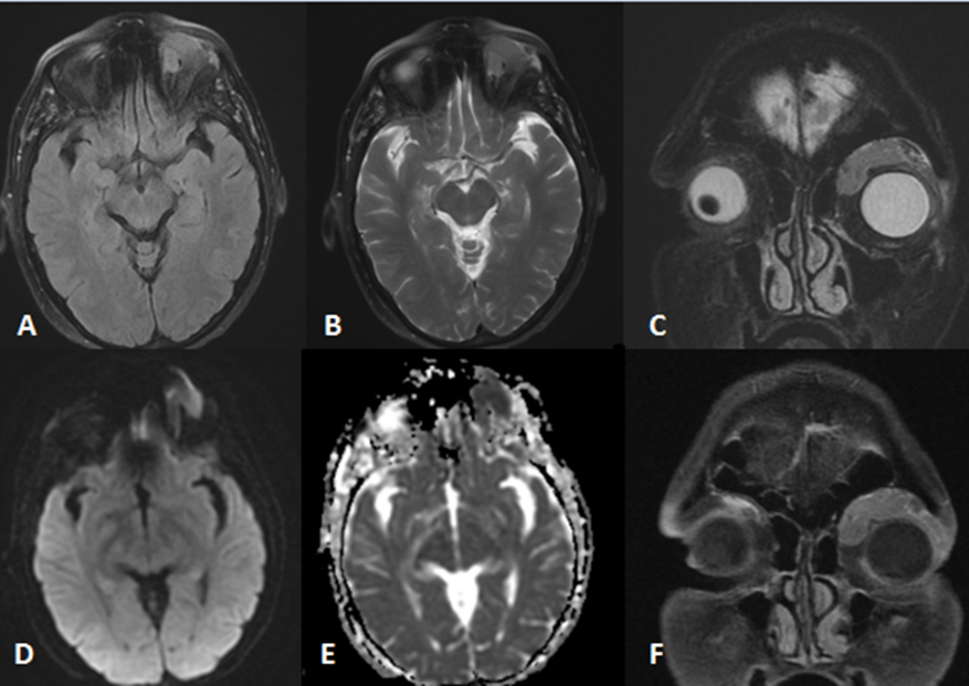

Figure 1: Axial FLAIR (A), axial T2 (B), coronal T2 (C), axial diffusion weighted sequence (D), axial ADC map (E), coronal T1 fat-sat postcontrast (F). A homogenous intraconal mass lesion located in the superior portion of the left orbit with mild mass effect over the globe. The mass lesion shows strong diffusion restriction in favor of hypercellularity. There is homogenous enhancement after contrast injection.